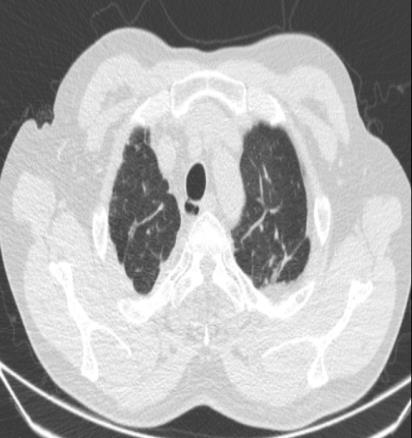

• 右肺中叶病变的临床特征分析(附709例报告)

2026, 32(3):45-50. DOI: 10.12235/E20250294

摘要 (42) HTML (59) PDF 1.50 M (41) 评论 (0) 收藏

摘要:目的 探讨右肺中叶支气管异常患者的人口学特征、临床表现、病因、影像学表现和支气管镜下表现。方法 回顾性分析2015年5月-2025年4月于该院在支气管镜检查中表现为右肺中叶异常改变的709例患者的临床资料,统计分析病因和临床特征。结果 709例患者中,男465例,女244例。男患者年龄(63.1±9.1)岁,明显高于女患者的年龄(60.9±11.5)岁,差异有统计学意义(P < 0.05)。临床表现主要包括:咳嗽、气促、咯血、痰中带血和胸痛,9.9%的患者未出现临床症状。根据年龄范围进行分组,将年龄 > 55岁的542例(76.4%)患者纳入高龄组,≤55岁的167例(23.6%)患者纳入低龄组,高龄患者明显多于低龄患者,差异有统计学意义(P < 0.05)。高龄组中,常见的3种病因分别为:肿瘤、炎症和结核。支气管镜下表现为:右中叶新生物、黏膜肥厚或肿胀、管腔狭窄和瘢痕闭塞等。结论 右肺中叶病变的患者采用影像学和支气管镜相结合的方式,对明确病因和指导临床治疗有重要意义。